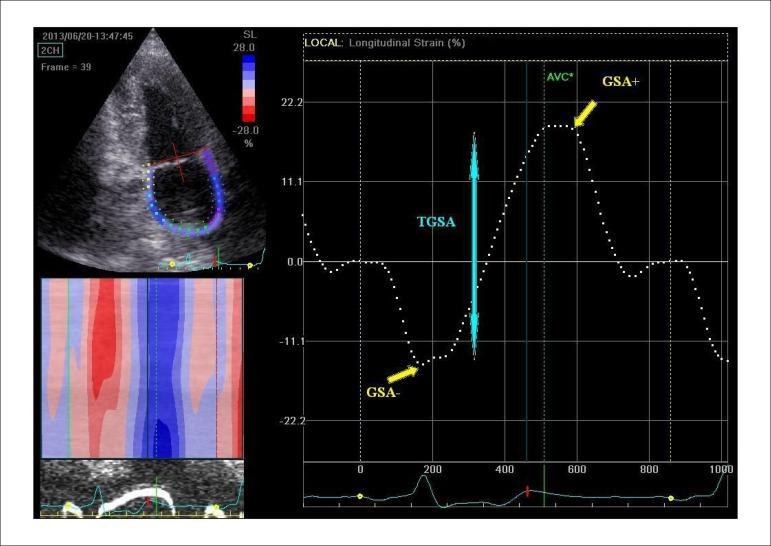

The assessment of left atrial (LA) function is used in various cardiovascular diseases. LA plays a complementary role in cardiac performance by modulating left ventricular (LV) function. Transthoracic two-dimensional (2D) phasic volumes and Doppler echocardiography can measure LA function non‑invasively. However, evaluation of LA deformation derived from 2D speckle tracking echocardiography (STE) is a new feasible and promising approach for assessment of LA mechanics. These parameters are able to detect subclinical LA dysfunction in different pathological condition. Normal ranges for LA deformation and cut-off values to diagnose LA dysfunction with different diseases have been reported, but data are still conflicting, probably because of some methodological and technical issues. This review highlights the importance of an unique standardized technique to assess the LA phasic functions by STE, and discusses recent studies on the most important clinical applications of this technique.

左心房(LA)功能评估应用于多种心血管疾病。LA通过调节左心室(LV)功能在心脏功能中发挥补充作用。经胸二维(2D)相位容积和多普勒超声心动图可无创测量LA功能。然而,基于二维斑点追踪超声心动图(STE)评估LA变形是一种评估LA力学的新的可行且有前景的方法。这些参数能够在不同病理状态下检测亚临床LA功能障碍。已有关于LA变形的正常范围以及诊断不同疾病LA功能障碍的临界值的报道,但数据仍存在冲突,这可能是由于一些方法学和技术问题。本综述强调了采用独特标准化技术通过STE评估LA相位功能的重要性,并讨论了关于该技术最重要临床应用的近期研究。